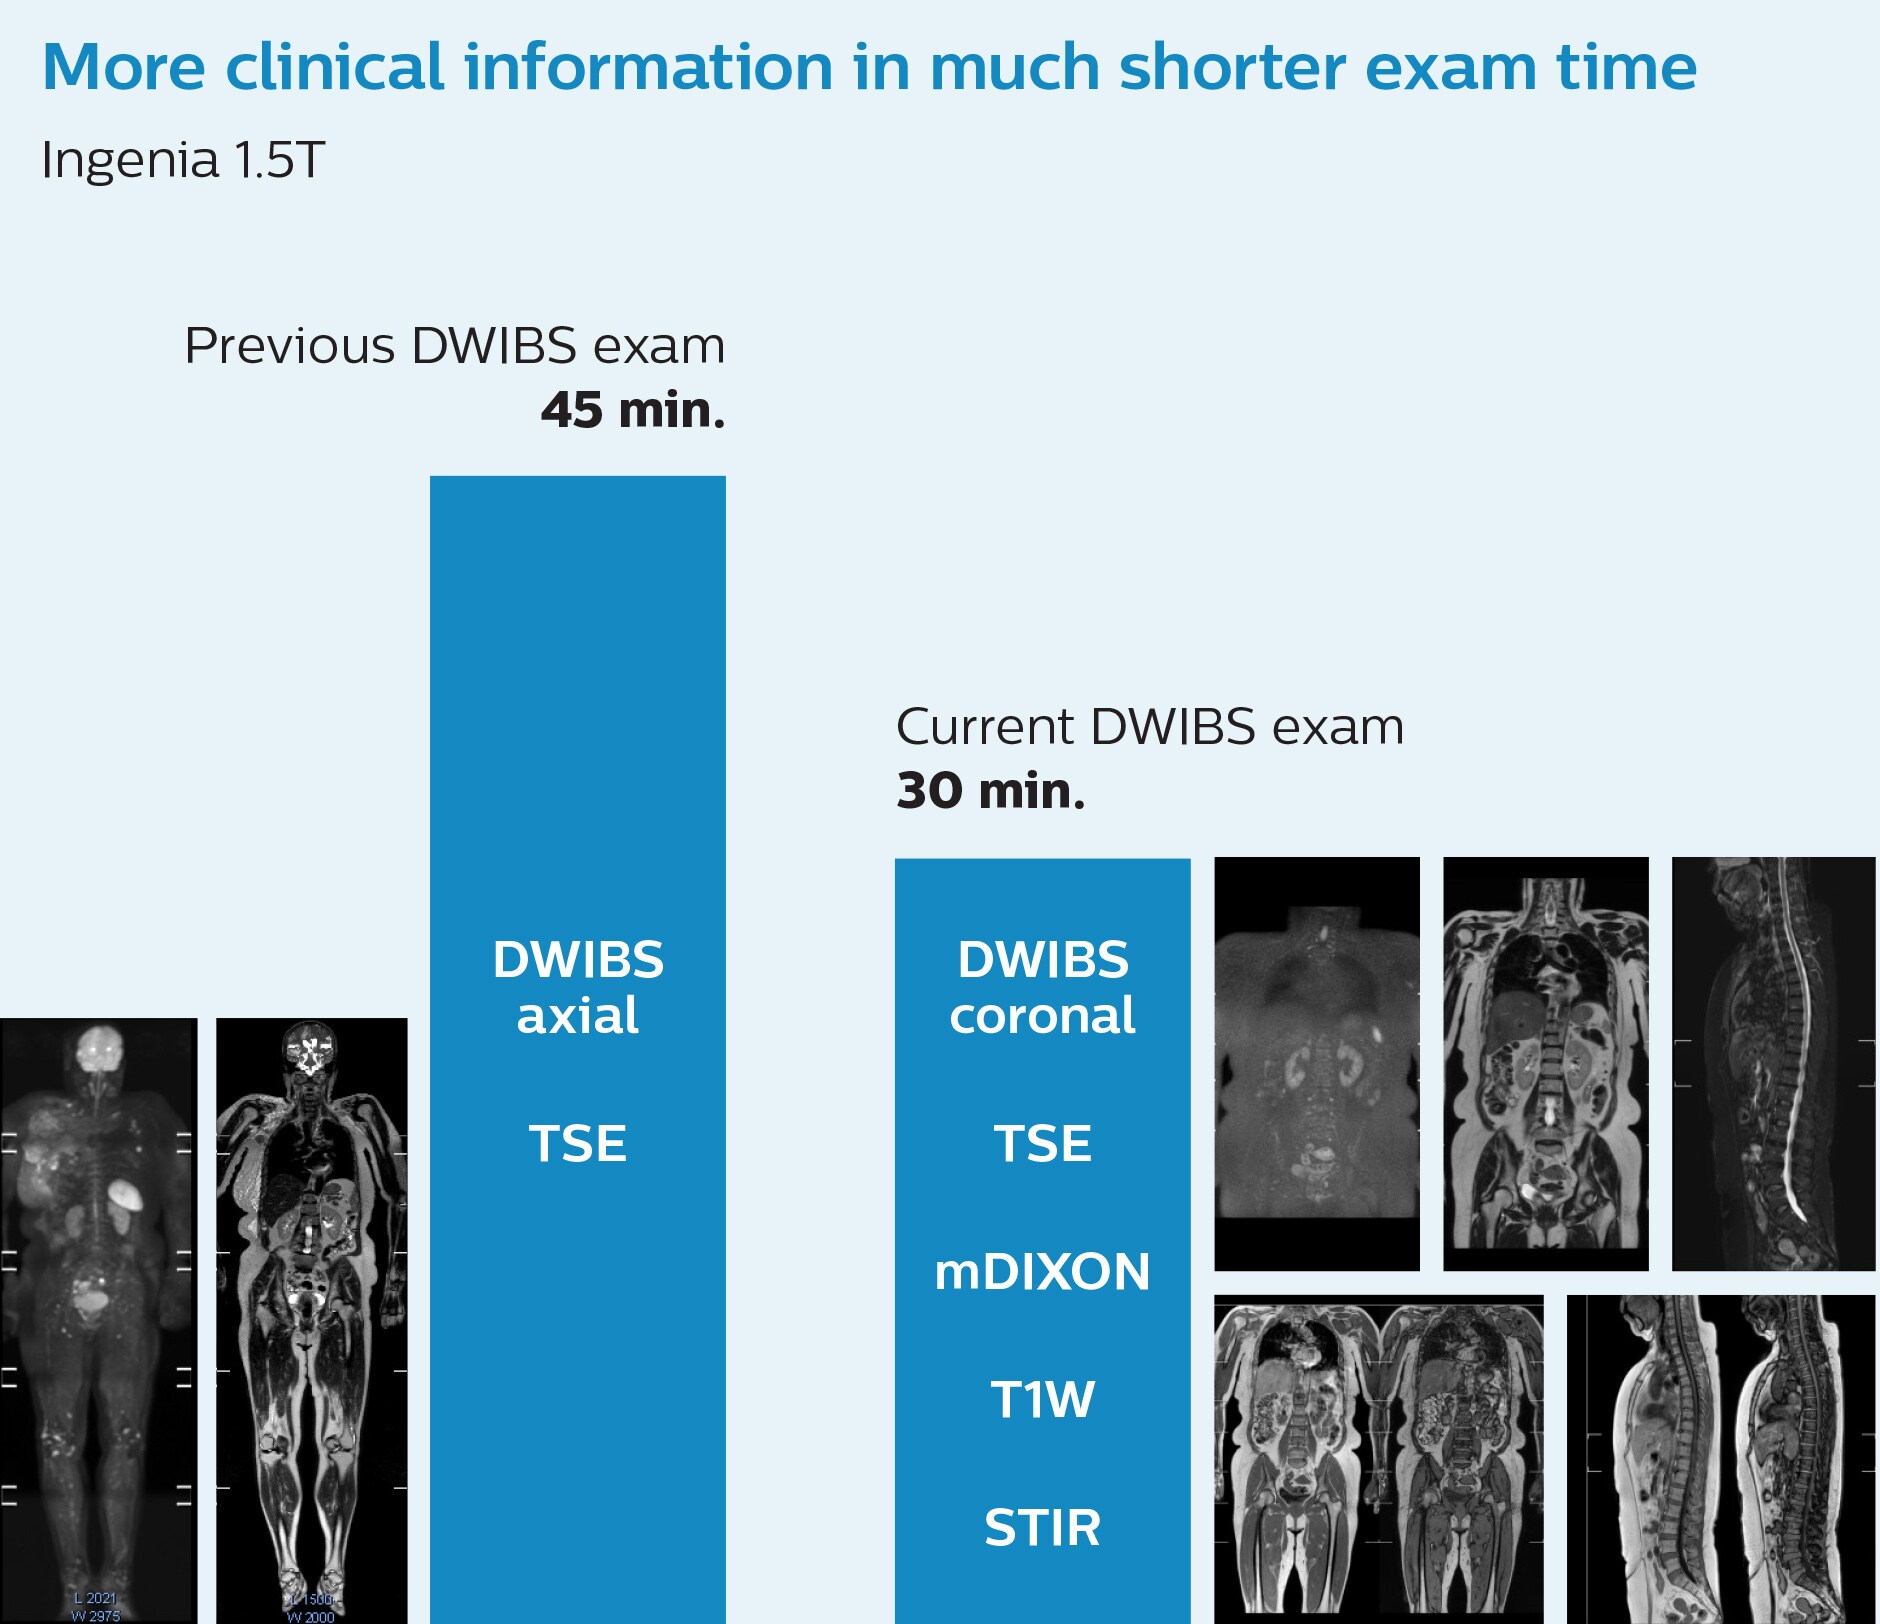

More clinical information in much shorter exam time

“When we limited the scan coverage to the area from neck to femur, we could fit more clinical information in approximately the same scan time. So, we added coronal mDIXON, sagittal T1-weighted, and sagittal STIR sequences to our examination, instead of performing only axial DWIBS and coronal single-shot TSE scans.” The single shot T2-weighted TSE images are used for morphology and compared to DWIBS images to identify T2 shine-through. Sagittal STIR images are used in patients with inflammation or bone metastasis.

“With coronal DWIBS, we can perform a full whole body exam, including other sequences, within 30 min.”

Coronal DWIBS is faster and improves image quality

“This is considerably faster than the previously used exam with axial whole body DWI, which took more than 45 minutes,” he notes. “A shorter exam is more patient-friendly and allows us to also use it on patients in poor health who would have difficulty tolerating a long exam. Limiting the exam time is also helpful for scheduling, because it fits in a normal single exam timeslot.”

“Switching to coronal DWIBS – rather than axial – further shortens scan time,” says Mr. Naka. “Important is that a dS SENSE factor of 5 shortens exam time while high image quality can be maintained, thanks to Ingenia’s dStream architecture.” He adds that the coronal orientation also avoids artifacts that are specific to combining axial images.

“When we use a coronal DWIBS acquisition, we can perform a full whole body examination, including other required sequences, within 30 minutes,” he says.